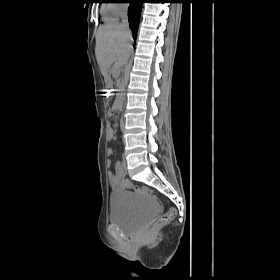

Radiological images:

CT-Scan investigation done on 16Apr16